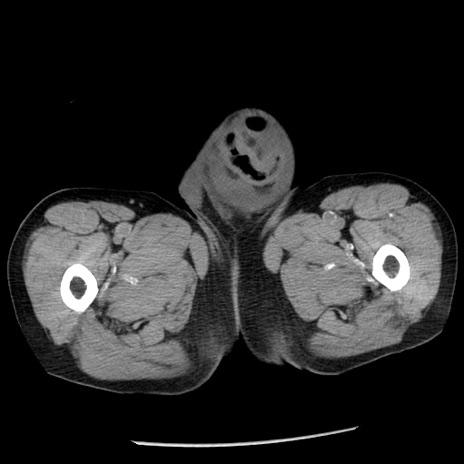

冠状断像

【症例】80歳代男性

【主訴】嘔吐

【現病歴】昨晩2回嘔吐あり、今朝になっても嘔吐あり。来院。

【既往歴】胃潰瘍

【身体所見】意識清明、BT 37.6℃、BP 166/95mmHg、HR 100bpm、SpO2 97%、腹部:平坦・軟、腸蠕動音聴取良好、圧痛なし。

【データ】WBC 21900、CRP 1.46